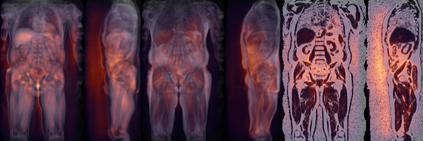

Along with rich health-related metadata, an ongoing imaging study has acquired MRI of over 40,000 male and female UK Biobank participants aged 44-82 since 2014. Phenotypes derived from these images, such as measurements of body composition, can reveal new links between genetics, cardiovascular disease, and metabolic conditions. In this retrospective study, six measurements of body composition were automatically estimated by ResNet50 neural networks for image-based regression from neck-to-knee body MRI. Despite the potential for high speed and accuracy, these networks produce no output segmentations that could indicate the reliability of individual measurements. The presented experiments therefore examine mean-variance regression and ensembling for predictive uncertainty estimation, which can quantify individual measurement errors and thereby help to identify potential outliers, anomalies, and other failure cases automatically. In 10-fold cross-validation on data of about 8,500 subjects, mean-variance regression and ensembling showed complementary benefits, reducing the mean absolute error across all predictions by 12%. Both improved the calibration of uncertainties and their ability to identify high prediction errors. With intra-class correlation coefficients (ICC) above 0.97, all targets except the liver fat content yielded relative measurement errors below 5%. Testing on another 1,000 subjects showed consistent performance, and the method was finally deployed for inference to 30,000 subjects with missing reference values. The results indicate that deep regression ensembles could ultimately provide automated, uncertainty-aware measurements of body composition for more than 120,000 UK Biobank neck-to-knee body MRI that are to be acquired within the coming years.